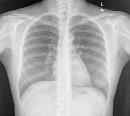

Table 3. Samples of CXR images from each dataset

Montgomery County, USA

Shenzhen, China

Konya, Turkey